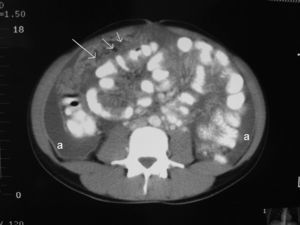

Presentamos el caso de una mujer de origen español de 26 años, sin antecedentes familiares ni personales de interés, que acude al servicio de urgencias de nuestro hospital por lumbalgia de 1 mes de evolución que no mejora con tratamiento con antiinflamatorios no esteroideos y que, en la última semana, concurren distensión abdominal, progresiva, indolora y fiebre de hasta 38°C de predominio vespertino. No refiere otra clínica digestiva ni síndrome general. El examen abdominal muestra ascitis a tensión y molestias abdominales difusas sin signos de irritación peritoneal. Los estudios analíticos, las radiografías de tórax y abdomen resultaron normales. Se procedió a una paracentesis evacuadora (negativa para células malignas, líquido ascítico, con características de trasudado y con adenosindesaminasa [ADA] de 2,7U/l). La tomografía computarizada (TC) abdominal informó de implantes tumorales difusos epiploicos y mesentéricos, ascitis masiva y quistes de 3cm en los ovarios (figs. 1 y 2), todo ello indicativo de carcinomatosis de posible origen ginecológico. Los marcadores tumorales fueron normales, excepto el CA 125 que tenía un valor de 517U/ml. La paciente fue intervenida, a los 15 días del ingreso, mediante laparoscopia de forma programada, en que se objetivó un gran bloqueo de asas intestinales e implantes de carcinomatosis en toda la zona, por lo que se consideró inviable una cirugía con intención curativa y se procedió a la toma de múltiples biopsias de implantes peritoneales y en el epiplón mayor. La anatomía patológica fue informada como peritonitis necrosante granulomatosa de origen tuberculoso. La evolución postoperatoria fue favorable y se le dio de alta al octavo día postoperatorio con tratamiento antituberculoso basado en isoniazida, pirazinamida, rifampicina y etambutol durante 6 meses. La paciente siguió en estudio y control, de forma ambulatoria, por el servicio de medicina interna, mediante pruebas radiológicas, broncoscópicas, con lavados y cepillados del árbol bronquial, determinaciones serológicas de los virus hepáticos y de la inmunodeficiencia humana, pruebas analíticas para valorar la función hepática, el ácido úrico, etc., sin objetivarse otros focos de tuberculosis, etiologías inmunosupresoras ni efectos secundarios por la medicación. La paciente tuvo el alta definitiva a los 12 meses. En la actualidad, y tras tantos meses de seguimiento, se encuentra asintomática y no precisa tratamiento alguno.

La ecografía y la TC evidencian hallazgos inespecíficos, el más frecuente es la ascitis, como sucedió con nuestra paciente. El análisis de la ascitis puede ser un exudado con predominio linfocítico1 o, como sucedió con nuestra paciente, un trasudado con cultivos negativos para BAAR. No obstante, algunos autores han publicado resultados de cultivos positivos en casos con paracentesis de más de 1l tras su centrifugado3. La ADA es una enzima degradadora de purinas necesaria para la maduración y la diferenciación de las células linfocíticas. La actividad de la ADA en líquido ascítico se ha propuesto como un método útil para la detección de la tuberculosis. Un metaanálisis de 12 estudios prospectivos, con 264 pacientes, encontró que el valor de la ADA tenía altas sensibilidad (100%) y especificidad (97%), con valores de corte entre 36 y 40U/l, el valor óptimo de corte fue 39U/l6. Hay falsos positivos en casos de cirrosis, peritonitis bacterianas espontáneas e infecciones por Chlamydia. Si la ADA es mayor de 50U/l, los falsos positivos son casi inexitentes4. Nuestra paciente presentaba una cifra de ADA en el líquido ascítico normal, 2,7U/l (normal, hasta 45U/l).